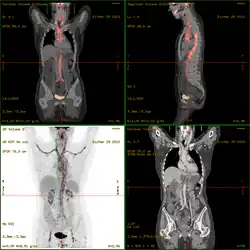

- Takayasu-Arteriitis als ANCA-negative Vaskulitis vor allem der Aorta und ihrer Hauptäste